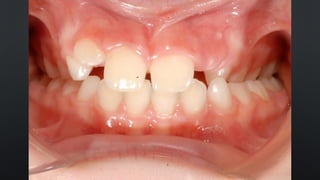

• FALTA DE ESPAÇO NO ARCO

• APINHAMENTO

RELAÇÃO INTERDENTAL

• POSICIONAMENTO PROMOVIDOPELA MUSCULATURA PERIORAL DURANTE A ERUPÇÃO • ESPAÇO NO ARCO • DENTE DIRECIONADO PARA A POSIÇÃO NEUTRA • FALTA DE ESPAÇO NO ARCO • APINHAMENTO RELAÇÃO INTERDENTAL